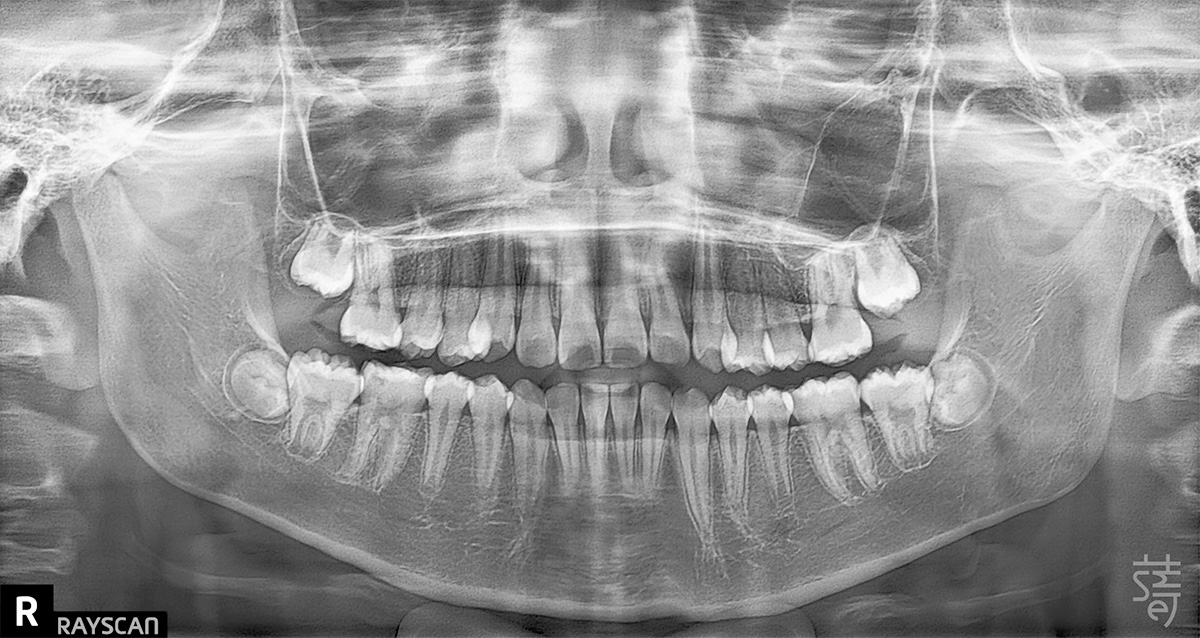

兩年後回診,X 光片上清楚顯示小緹的牙列變整齊了、牙弓更開展,嘴型也能自然閉合。那些早期努力的累積,就這樣安靜卻確實地發生在孩子身上。

Two years later, Ti returned for a follow-up, and the X-rays told the story clearly: a broader arch, straighter teeth, and a relaxed, natural lip seal. The quiet, steady work of early treatment had taken root.

媽媽笑著分享:「兩年間小緹改變很多,慢慢長出自信,各種場合總能自在露齒笑!」她很慶幸自己在孩子的早期階段,做了這個正確的決定。

Her mother put it simply—Ti was still shy, but she carried herself with more ease, smiling freely in a way that felt new and self-assured.